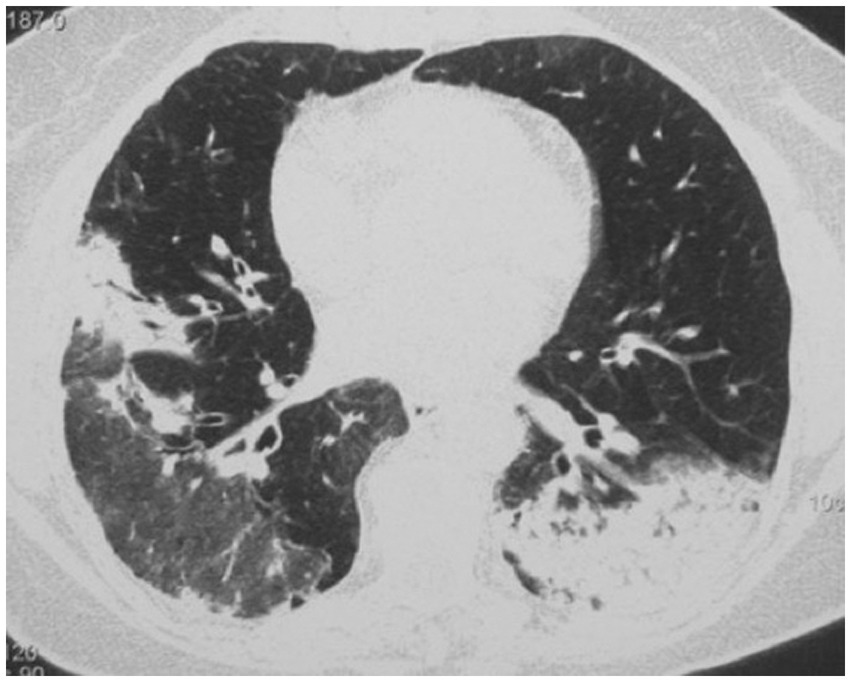

High-resolution computed tomography (HRCT) is the gold standard in the evaluation of OP. It reveals multifocal areas of consolidation, often with a characteristic air bronchogram. Additionally, patchy alveolar consolidations, nodules, areas of ground glass opacity, perilobular infiltrations, bronchial wall thickening, and reticular fibrous changes may be present in peripheral parts of both lungs. Thickening around areas of ground glass opacity with an “atoll” or “crazy-paving” pattern may also be present, although it is less common. Additionally, nodular lesions, pleural thickening, and rarely enlargement of hilar and mediastinal lymph nodes, are present; emphysema or pleural effusion may also be observed (28–40). Honeycomb-type lesions are not in the spectrum of pulmonary changes observed in COP but might be evident in patients who exhibit interstitial pulmonary fibrosis with a component of OP (Figures 2–6).

High resolution computed tomography scan of a patient with COP. Massive bilateral opacities with presence of air bronchogram and accompanying ground glass opacities on the right lung.